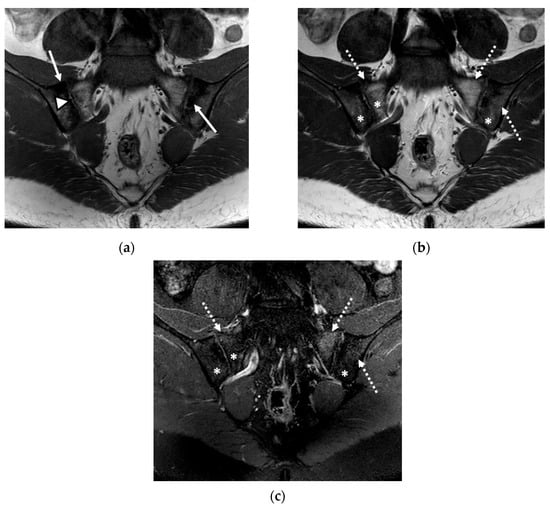

We evaluated 68 sacroiliac joints. The prevalence of MRI-detected abnormalities is presented in Table 2. The results of the SR were considered as the reference data. Inflammatory and structural changes were detected on the MRI sequences of the sacroiliac joints. The most frequently encountered inflammatory change, both on the left and right sacroiliac joint, was the presence of bone marrow edema (44.11–58.82%), followed by enthesitis (17.64–26.47%) and synovitis (11.76–17.64%). Regarding structural changes, the most prominent was subchondral sclerosis (50–59.37%), followed by erosions (35.29–41.17%), joint space narrowing (38.23%), fat metaplasia (17.64–23.25%), and backfill (11.76–20.58%) (Figure 1, Figure 2 and Figure 3).

Figure 2.

The MRI scan of the sacroiliac joints indicated bilateral narrowing of the sacroiliac joint space, associated with bilateral subchondral sclerosis of the iliac bones (continuous arrow); bilateral fat metaplasia (asterisk), mostly affecting the iliac bones and the right part of the sacrum; backfill of the right sacroiliac joint space (arrowhead); diffuse bone marrow edema (discontinuous arrow), affecting the sacrum and the left iliac bone: (a) T1-weighted sequence; (b) T2-weighted sequence (without fat suppression); (c) STIR sequence.